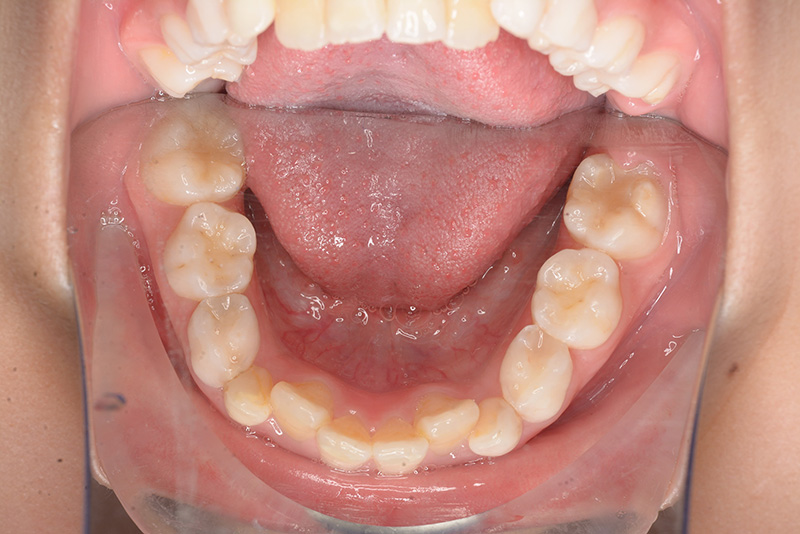

| パノラマ所見 | 上顎両側6、特に左側6は近心傾斜が認められ、両側5の萌出スペース不足が認められた。 |

| 批評・予后 | 早期に6の遠心移動を行いナンスのホールディングアーチにて保隙をした結果、5は良好な状態で萌出できたように思う。 今後は永久歯列完成まで経過観察を行っていく予定である。 |